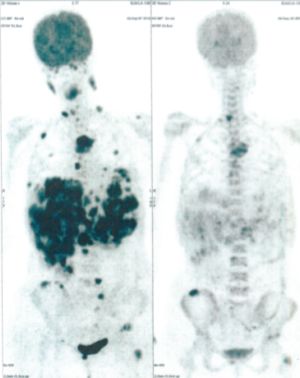

Below are some of the cases, from more than 80 cases we have treated so far with good results. When reading the PET/CT scans, the picture on the left is before treatment, and the picture on the right is after treatment. The intensity of black represents the activity of the cancer, but some black areas are not cancer: brain, heart, radioactive urine in bladder. For the heart, the intensity of black depends on the number of hours of fasting: if more than 10 hours, the heart is not even black, but if fasting is less than 6 hours, it is very black. The intensity of black in the brain can be variable in different scans depending on the brain activity at the time of the scan. The intensity of black in the radioactive urine can also be variable due to the hydration of patients and the time of injection of diuretic.

CASE NO: 1

(HEPATOCELLULAR CARCINOMA + STOMACH CANCER)

A middle-aged women who is very thin and very weak, can hardly walk, lying in bed most of the time. She saw a cancer specialist in a top hospital who discovered that she had massive hepatocellular carcinoma, and another cancer in the stomach. Given that hepatocellular carcinoma is incurable and stomach cancer is very difficult if not impossible to cure without surgery, she was told that nothing could be done for her. She came to ask us to help her. After just 4 treatment, the hepatocellular carcinoma went into remission, and the stomach cancer (arrow) became less active. Until today, more than 6 months later, the hepatocellular carcinoma is still in remission.